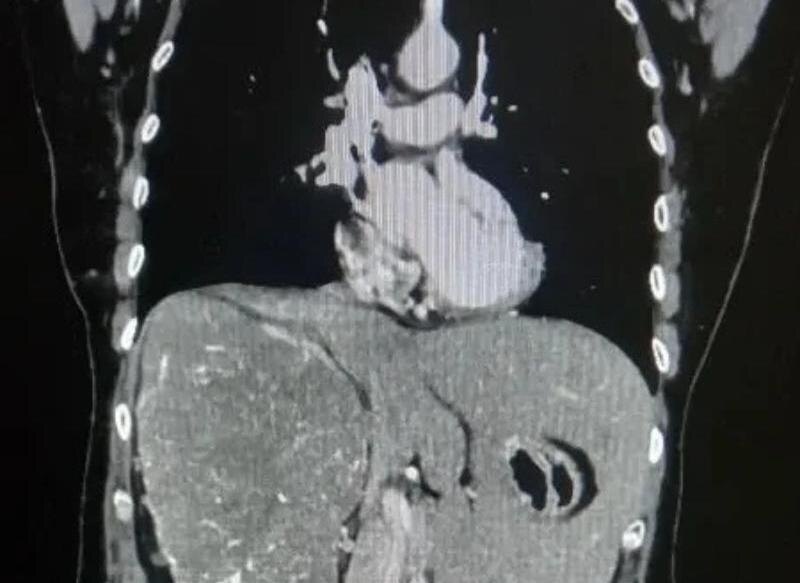

Врачи Волгоградского областного онкологического диспансера провели сложную операцию пациентке с гигантской опухолью почки. Новообразование достигло таких размеров, что сместило внутренние органы: печень оказалась вытеснена из правой части брюшной полости в левую.

Женщина долгое время жаловалась на тупую боль в пояснице и чувство тяжести в животе. После обследования с помощью компьютерной томографии врачи обнаружили крупную опухоль, которая практически полностью заняла правую сторону брюшной полости. Исследования показали, что функция правой почки была почти полностью утрачена. Размер новообразования составил более 20 сантиметров. Медики приняли решение о проведении операции. Из-за больших размеров опухоли выполнить вмешательство малоинвазивным способом было невозможно, поэтому хирурги провели открытую операцию — радикальное удаление правой почки.

Операцию выполнила команда специалистов онкоурологического отделения. Несмотря на сложность случая, хирургам удалось полностью удалить опухоль. По результатам гистологического исследования был подтверждён диагноз — светлоклеточная карцинома. При этом новообразование не успело прорасти в соседние органы, а лишь сильно сместило их, сообщили в пресс-службе облздрава Волгоградской области.